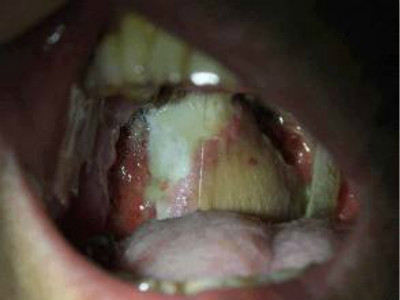

扁桃體惡性腫瘤圖片

扁桃體癌圖 (69)